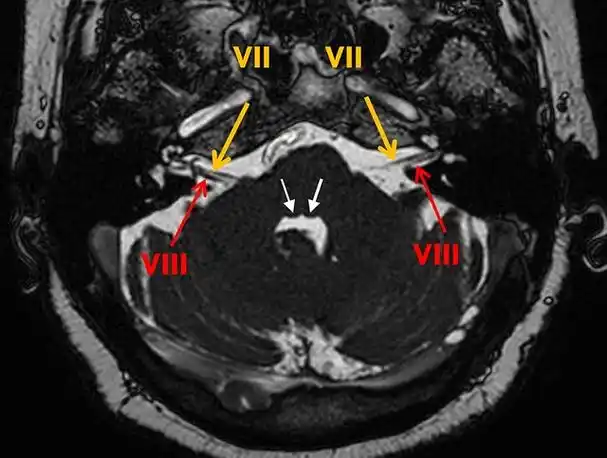

面神经解剖与常见疾病

该病典型的 mri 表现为双侧面神经发育不全,在平衡稳态梯度回波序列

12对颅神经连续层面mri解剖